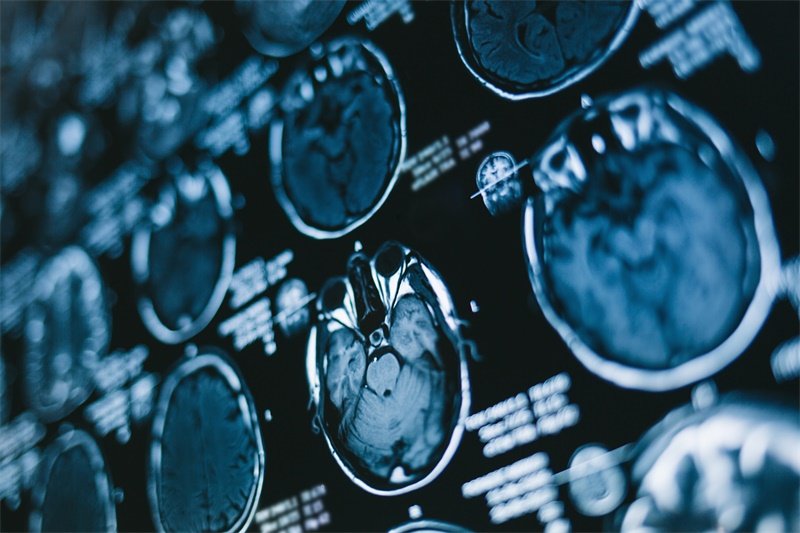

为了确定右侧颞骨蝶骨区的占位情况,医生通常建议采取一系列检查。影像学检查是首要的手段,常用的有CT(计算机断层扫描)和MRI(磁共振成像)等。

CT检查通常能够迅速了解占位的存在、位置及其特征,而MRI则能提供更加清晰的软组织对比,帮助判断占位的性质及周围组织的关系。